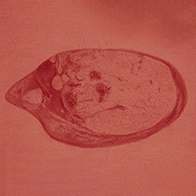

The most common presentation of gynecological adnexal masses are ovarian cysts, which form on the ovaries post-ovulation. "A cyst can make the ovary unbalanced and lead to twisting," Lumumba-Kasongo explained.

"Studies have shown the risk increases in cysts greater than 5 cm," Vakharia stated. "At some point in the range of cyst sizes, the opposite may then become true as it has been suggested that extremely large cysts may be less likely to torte due to insufficient space in the pelvis."